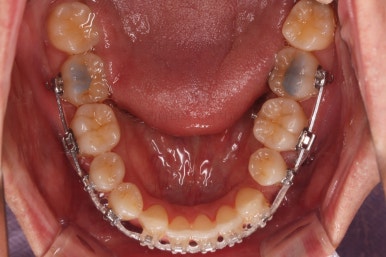

점점 마무리에 가까워지고 있습니다.

화살표는 사랑니인데요. 이 분의 경우 아래 앞니가 1개 없고, 1개를 추가로 뽑아서 윗니 대비 아랫니가 총 2개 모자란거죠.

운이 좋게도 이 분은 사랑니까지 잘 나와있던 상태라 내버려두기 아까워 함께 가지런하게 해주고 사용하실 수 있게 해드렸어요.

좀 더 마무리를 하고 치료 종료하기로 했어요.